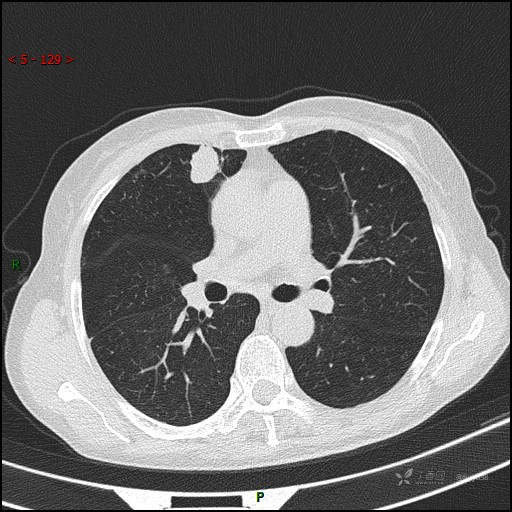

胸部CT平扫